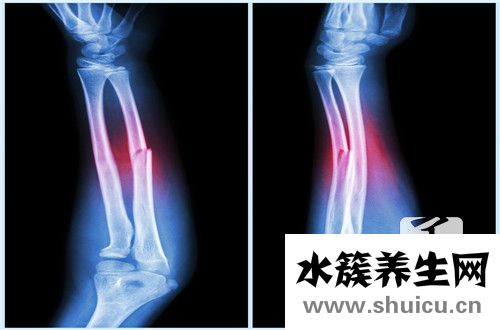

右撓骨遠端骨折在生活當中比較常見,占總的骨折大約1/10左右.多見一些中老年人,尤其是老年女性,因為骨質(zhì)疏松的原因,很可能發(fā)生這個部位發(fā)生骨折,相對來說是比較嚴重的,因為發(fā)生骨折以后會導致脹痛等現(xiàn)...